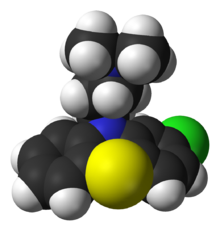

The mainstay of treatment is antipsychotic medication, which primarily suppresses dopamine (and sometimes serotonin) receptor activity. Psychotherapy and vocational and social rehabilitation are also important in treatment. In more serious cases—where there is risk to self and others— involuntary hospitalization may be necessary, although hospital stays are now shorter and less frequent than they once were.

Particular attention has been paid to the function of dopamine in the mesolimbic pathway of the brain. This focus largely resulted from the accidental finding that phenothiazine drugs, which block dopamine function, could reduce psychotic symptoms. It is also supported by the fact that amphetamines, which trigger the release of dopamine, may exacerbate the psychotic symptoms in schizophrenia. The influential dopamine hypothesis of schizophrenia proposed that excessive activation of D2 receptors was the cause of (the positive symptoms of) schizophrenia. Although postulated for about 20 years based on the D2 blockade effect common to all antipsychotics, it was not until the mid-1990s that PET and SPET imaging studies provided supporting evidence. The dopamine hypothesis is now thought to be simplistic, partly because newer antipsychotic medication ( atypical antipsychotic medication) can be just as effective as older medication ( typical antipsychotic medication), but also affects serotonin function and may have slightly less of a dopamine blocking effect.

Interest has also focused on the neurotransmitter glutamate and the reduced function of the NMDA glutamate receptor in schizophrenia, largely because of the abnormally low levels of glutamate receptors found in the postmortem brains of those diagnosed with schizophrenia, and the discovery that glutamate-blocking drugs such as phencyclidine and ketamine can mimic the symptoms and cognitive problems associated with the condition. Reduced glutamate function is linked to poor performance on tests requiring frontal lobe and hippocampal function, and glutamate can affect dopamine function, both of which have been implicated in schizophrenia, have suggested an important mediating (and possibly causal) role of glutamate pathways in the condition. But positive symptoms fail to respond to glutamatergic medication.